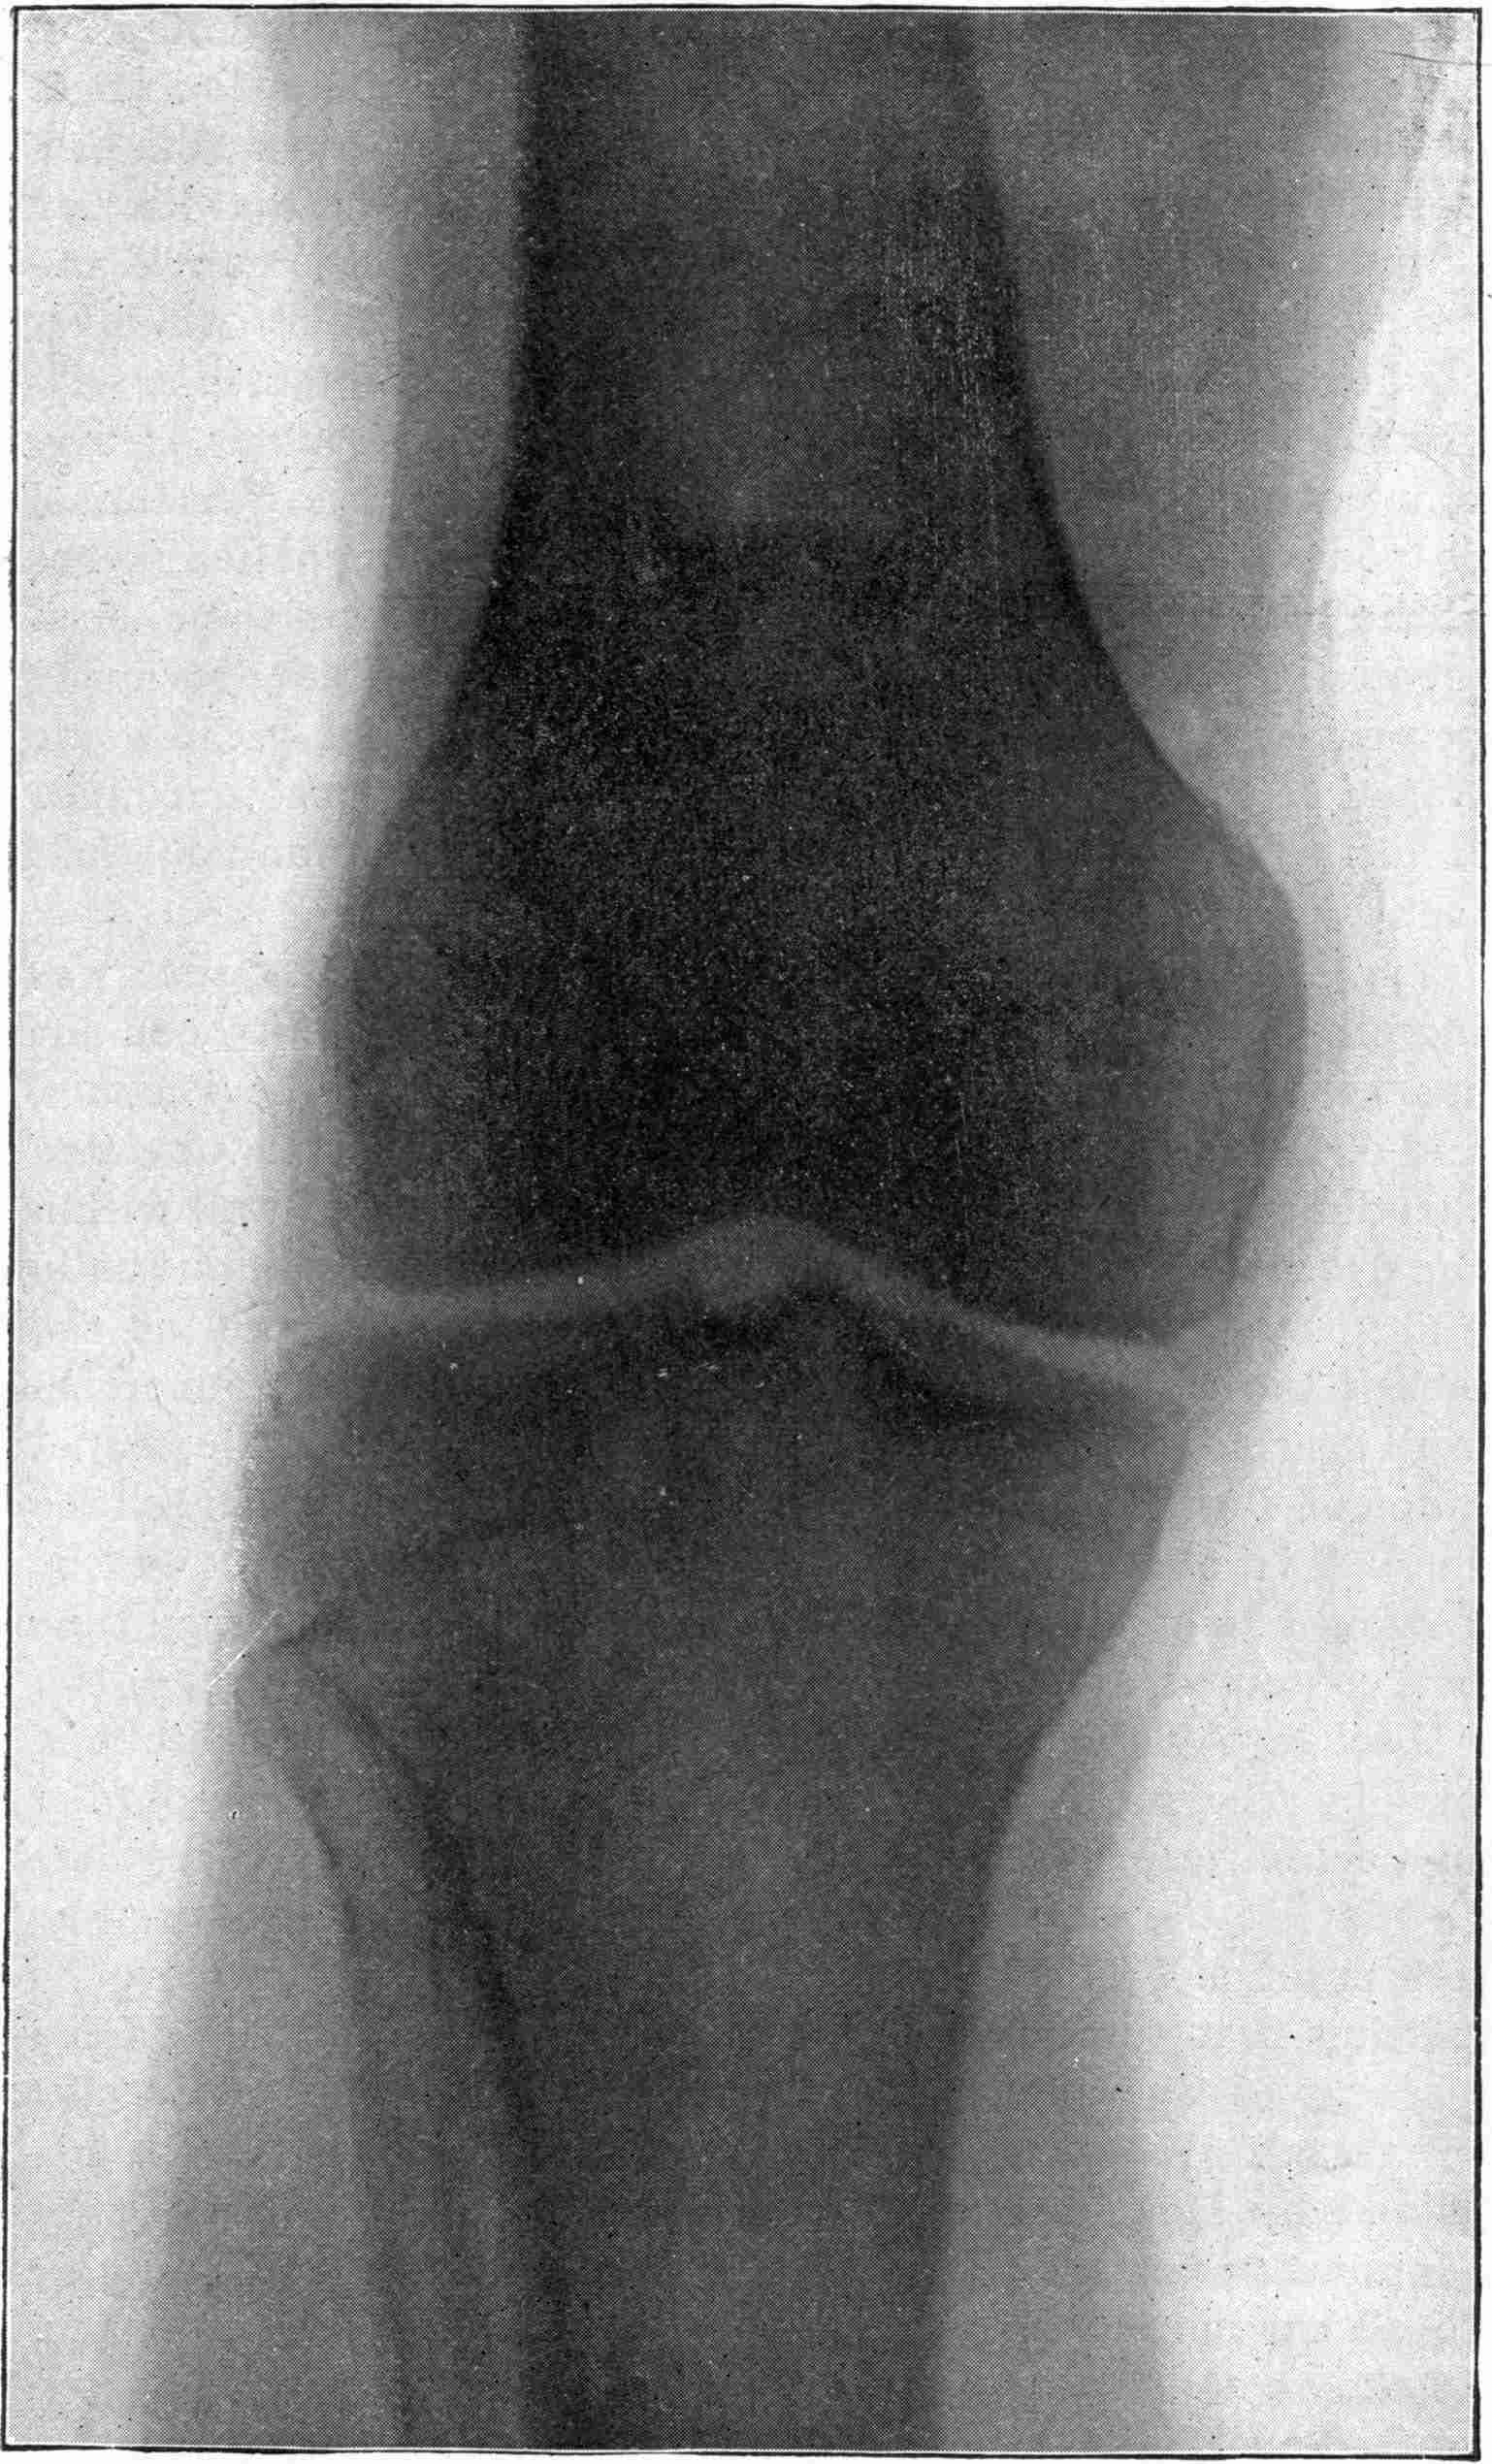

Fig. 4.—Knee, Knickerbocker Buttons, Bullet in Femur.

| 204. | Bones in Apposition Discovered by X-rays and afterward Remedied by Operation. Other Cases. | Miller |

| 204a. | Necrosis. | Miller |